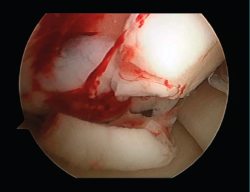

First surgery involves arthroscopy of the damaged joint. It assesses the chondral lesion to be treated and confirms whether it is amenable to the chondrocyte implantation technique (Figures 1 and 2). Other procedures are also carried out if needed, such as for example reconstruction of the anterior cruciate ligament, partial meniscectomies, meniscus implantation, patellar realignments, osteotomies, etc. Lastly, the cartilage sample is taken from a non-weight bearing zone (intercondylar zone or internal femoral condyle at its upper margin). The sample is extracted with biopsy forceps or, alternatively, using discectomy forceps. Between 3-4 rice grain-sized fragments of healthy cartilage are harvested (Figure 3). The biopsy material is placed in a sterile receptacle containing a culture medium (DMEN) (Figure 4). The material is kept at room temperature and is shipped to the laboratory as quickly as possible. A form should be completed (Figure 5), stating the joint, the location of the lesion and the size of the defect. Once in the laboratory, the sample is processed and cultured. After 4-6 weeks (depending on the case), the culture is ready for implantation.

2. The damaged cartilage is cleaned using curettes, with debridement of the defect, and the lesion is left with healthy and exposed subchondral bone (Figure 7).